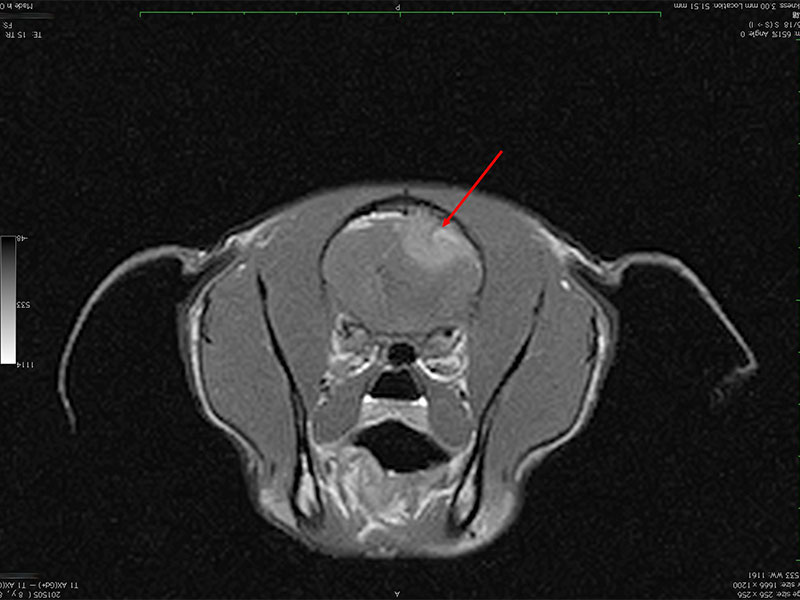

頭部

● 検査

CT、MRI、超音波

● 疾患

水頭症、腫瘍、癲癇

神経症状(発作、けいれん)や歩行障害がでる。癲癇や水頭症との鑑別のために、CTやMRIで検査する。